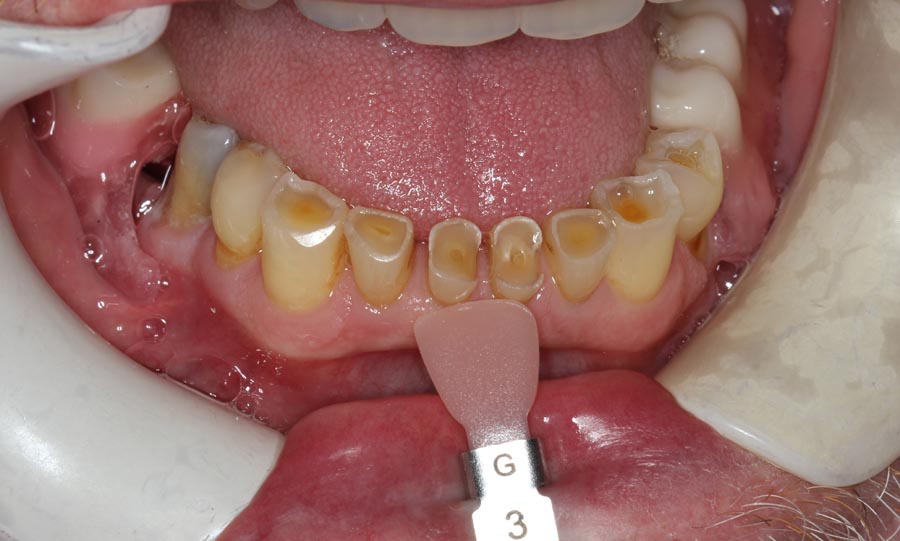

The lower teeth were bonded with composite resin to improve aesthetics and function during the year he is waiting to do his lower.